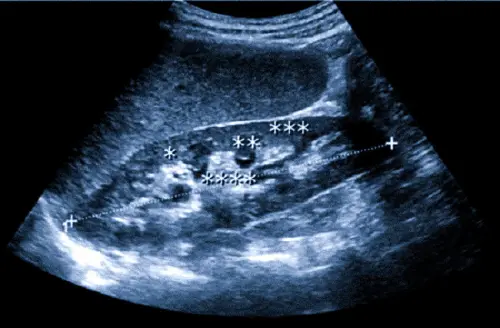

Продолжительность процедуры составляет 20-30 минут. Это делает метод диагностики почек быстрым и комфортным для пациента. УЗИ проводится в удобном положении лежа, поочередно на спине и на боку.

Врач наносит специальный гель на область исследования и проводит сканирование с помощью ультразвукового датчика.

Во время процедуры пациент может ощущать легкое давление датчика, но болезненных ощущений не возникает. Это отвечает на вопрос "больно ли делать УЗИ почек". Врач-диагност внимательно изучает все отделы исследуемых органов, делает необходимые замеры и фиксирует выявленные изменения. Такой подход позволяет получить полную картину о том, что показывает УЗИ почек.

Оборудование, используемое в клинике Астрамедика, позволяет получать изображения высокого разрешения и проводить допплерографию почек для оценки кровотока.